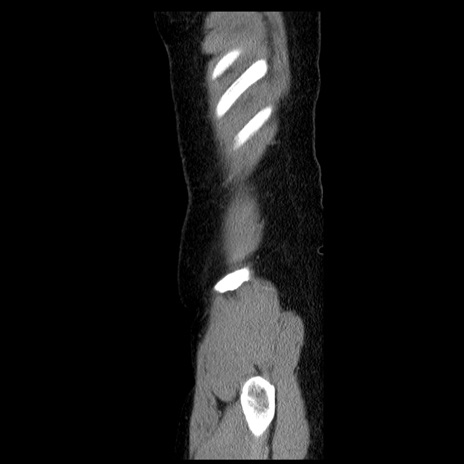

横断像